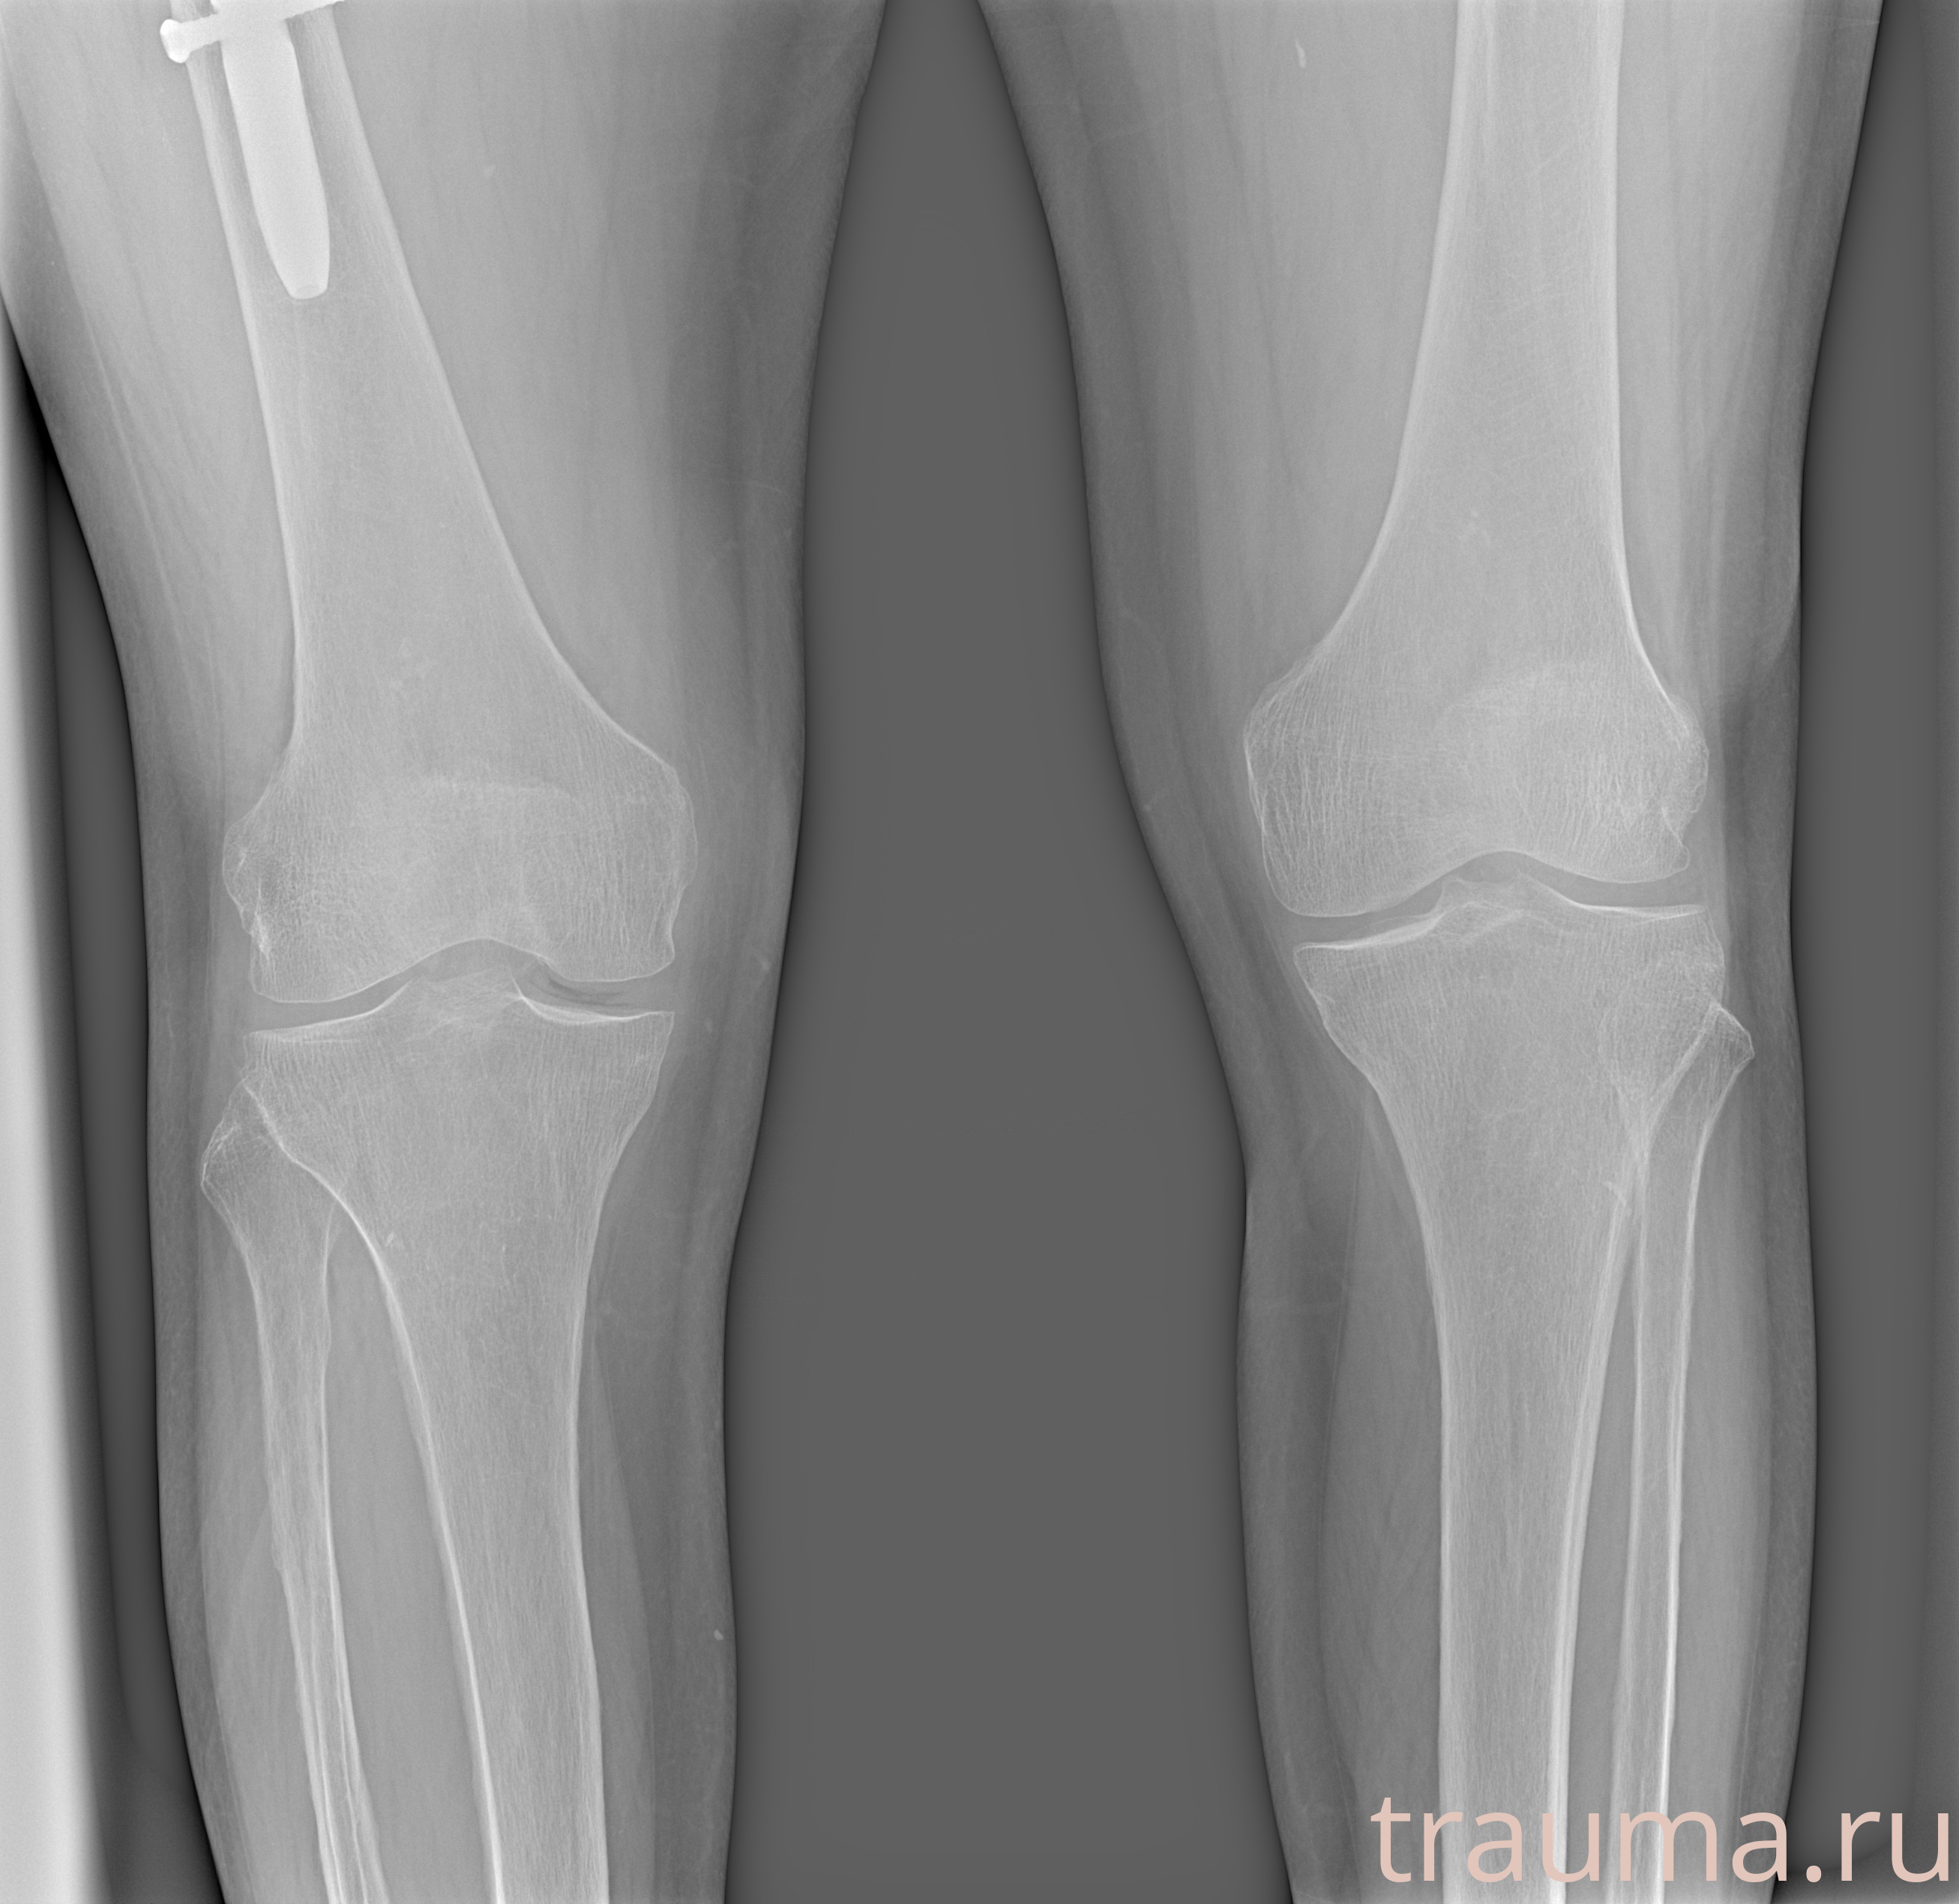

Рентгенограммы

Рентген на дому: по вашему адресу приезжает врач-рентгенолог, травматолог-ортопед с мобильным рентгеновским аппаратом, проводит диагностику травмы или заболевания, делает необходимые рентгенограммы, дает рекомендации по дальнейшему лечению. Получить качественные снимки в домашних условиях возможно благодаря уникальной методике, разработанной МосРентген Центром для института  Склифосовского